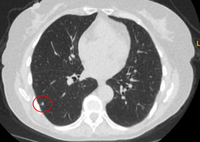

Tomografia computadorizada (TC) mostrando nódulo alongado periférico no lobo superior esquerdo, com captação de contraste e lado de alimentação e drenagem nítido, condizente com pequena malformação arteriovenosa

Do acervo de Dr. George Tsaknis, MD, PhD, FRCP (Londres), MRQA, MAcadMEd, PGCert; usado com permissão